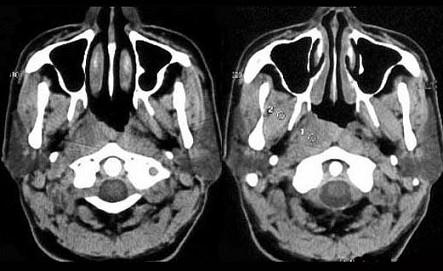

男,52岁,右耳鸣两月余,伴鼻塞,CT如图所示,应诊断为()A.鼻咽淋巴瘤B.鼻咽纤维血管瘤C.增殖体肥大D.鼻咽癌E.鼻咽部慢性炎症

问题 男,52岁,右耳鸣两月余,伴鼻塞,CT如图所示,应诊断为()

选项 A.鼻咽淋巴瘤 B.鼻咽纤维血管瘤 C.增殖体肥大 D.鼻咽癌 E.鼻咽部慢性炎症

答案 D